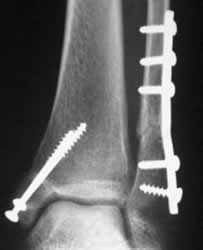

Fig 99. Tornillos de esponjosa y de cortical.

Rx AP. Fractura bimaleolar. La del medial está fijada con tornillos de esponjosa y la del lateral, con placa y tornillos de cortical.